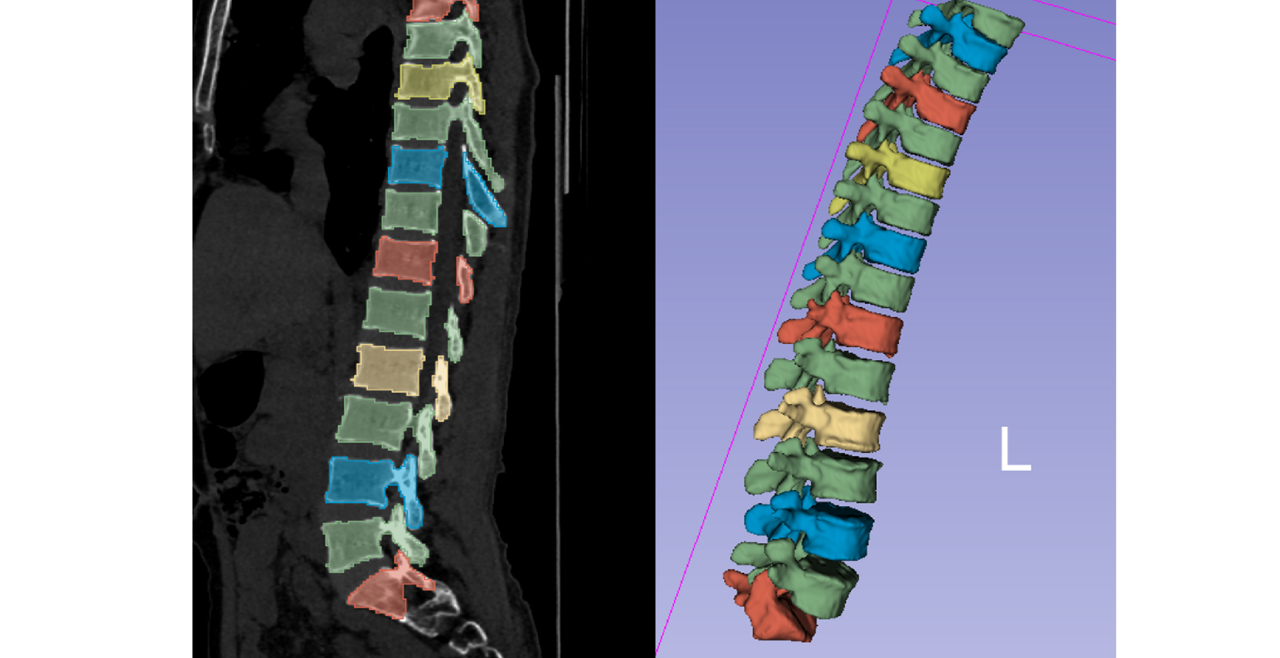

Our current research projects include: advancing a new regulatory pathway for conduct of osteoporosis clinical trials, testing advanced imaging techniques for assessing skeletal fragility, examining the effects of musculoskeletal health in disuse and spaceflight, understanding stress fracture mechanisms in military recruits, and investigating musculoskeletal health in indigenous populations.